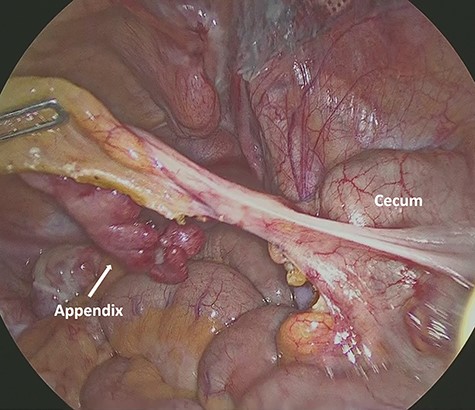

A 1.5-cm intraumbilical incision was made under general anesthesia, and the subcutaneous tissue and the anterior rectus sheath were dissected. The right rectus abdominis was moved to the lateral side, and a 12-mm trocar was inserted into the extraperitoneal space. Thereafter, two 5-mm working trocars were inserted into the midline of the lower abdomen. The insufflation pressure was set at 10 cm H2O. Under a 30-degree telescopic vision, the preperitoneal space was dissected to the inguinal region using an ultrasonically activated device. This revealed the incarcerated hernia sac in the femoral canal (Fig. 2). Because replacing the sac from the femoral canal was difficult, the lacunar ligament was divided. After the femoral ring widened, the sac was safely repositioned into the abdominal space; a 10 × 13 cm mesh (SURGIMESH XD®, Neomedica Co., Roma, Mexico) was placed without tackers to cover the space. Following the preperitoneal approach, we reinserted the 12 mm trocar into the abdominal cavity, and the other trocars were replaced to the left lower abdomen (Fig. 3). Exploration of the abdominal cavity revealed an inflamed appendix, and erythema was clearly recognized in the distal half, proving that appendicitis was caused by compression. There were no findings of necrosis, perforation or abscess formation (Fig. 4). Appendectomy was performed safely. Additionally, mesh repair was confirmed as successful through the peritoneum and there were no other coexisting hernia. The patient recovered uneventfully and was discharged on postoperative Day 3. Histopathological examination revealed moderate inflammation of the appendix.

Intra-abdominal view shows the inflamed appendix without any symptoms of necrosis, perforation or abscess formation.